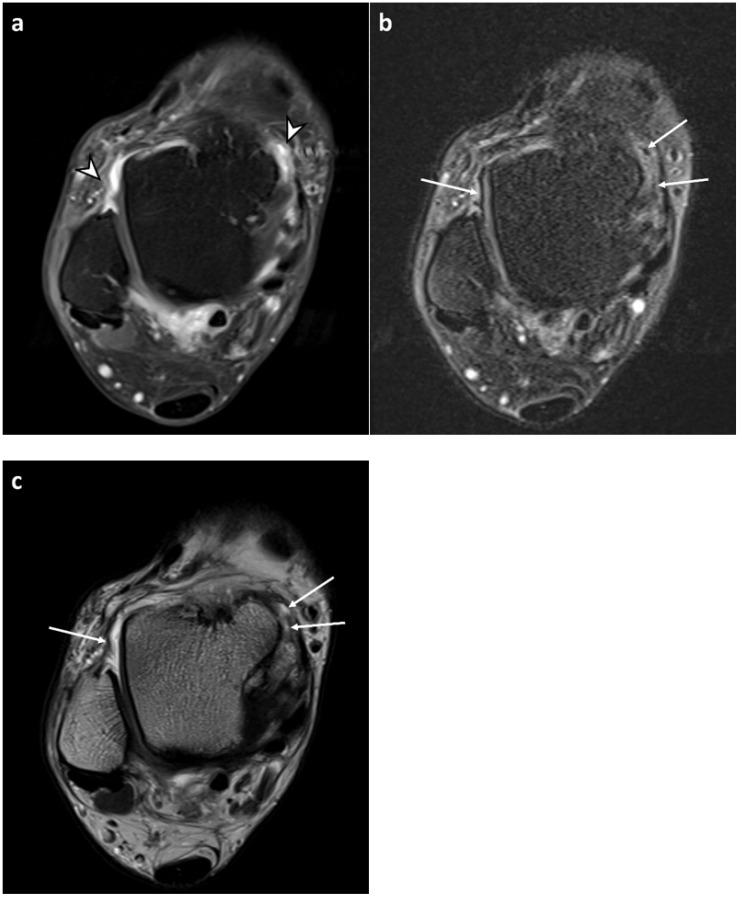

The purpose of this study was to investigate the feasibility of the fluid-attenuated inversion recovery sequence with fat suppression (FLAIR-FS) for the assessment of ankle synovitis without contrast enhancement. FLAIR-FS and contrast-enhanced, T1-weighted sequences (CE-T1) of 94 ankles were retrospectively reviewed by two radiologists. Grading of synovial visibility (four-point scale) and semi-quantitative scoring of synovial thickness (three-point scale) were performed in four compartments of the ankle in both sequences. Synovial visibility and thickness in FLAIR-FS and CE-T1 images were compared, and agreement between both sequences was assessed. Synovial visibility grades and synovial thickness scores for FLAIR-FS images were lower than those for CE-T1 images (reader 1, = 0.016, < 0.001; reader 2, = 0.009, < 0.001). Dichotomized synovial visibility grades (partial vs. full visibility) were not significantly different between both sequences. The agreement in synovial thickness scores between the FLAIR-FS and CE-T1 images was moderate to substantial (κ = 0.41-0.65). The interobserver agreement between the two readers was fair for synovial visibility (κ = 0.27-0.32) and moderate to substantial for synovial thickness (κ = 0.54-0.74). In conclusion, FLAIR-FS is a feasible MRI sequence for the evaluation of ankle synovitis without contrast enhancement.

本研究的目的是探讨脂肪抑制液体衰减反转恢复序列(FLAIR-FS)在不使用对比剂增强的情况下评估踝关节滑膜炎的可行性。两名放射科医生对94例踝关节的FLAIR-FS和对比增强T1加权序列(CE-T1)进行了回顾性分析。在两个序列中,对踝关节的四个腔室进行滑膜可见性分级(四分制)和滑膜厚度的半定量评分(三分制)。比较FLAIR-FS和CE-T1图像中的滑膜可见性和厚度,并评估两个序列之间的一致性。FLAIR-FS图像的滑膜可见性分级和滑膜厚度评分低于CE-T1图像(读者1, = 0.016, < 0.001;读者2, = 0.009, < 0.001)。两个序列之间滑膜可见性分级的二分法(部分可见与完全可见)无显著差异。FLAIR-FS和CE-T1图像之间滑膜厚度评分的一致性为中度至高度(κ = 0.41 - 0.65)。两位读者之间的观察者间一致性在滑膜可见性方面为一般(κ = 0.27 - 0.32),在滑膜厚度方面为中度至高度(κ = 0.54 - 0.74)。总之,FLAIR-FS是一种在不使用对比剂增强的情况下评估踝关节滑膜炎的可行MRI序列。